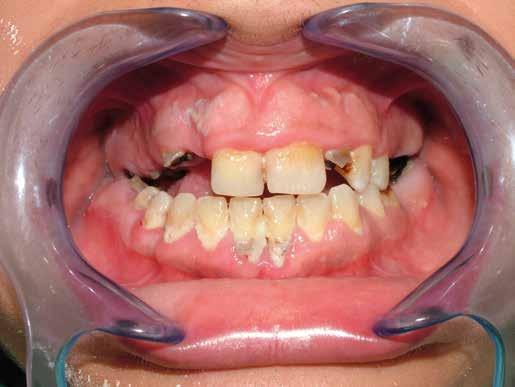

Alla visita di rivalutazione è emerso un ulteriore peggioramento della situazione, confermata anche dall’esame radiografico, con parodontopatia, sanguinamento al sondaggio, infiammazione diffusa, alitosi, difetto parodontale verticale mesiale a 2.3, residui radicolari 1.4, 1.6, 1.7, 3.6, 3.8 e carie destruenti di 1.5, 2.6, 3.5, 3.7 (con lesione endoperio) e 4.7 con estrusione e carie (Figg. 1, 2)

Il paziente, un uomo di 67 anni, ha confermato l’anamnesi precedente, ossia di essere portatore di

molteplici patologie: sindrome metabolica in discreto compenso farmacologico (riferita assunzione di metformina 500 mg, enalapril, acido acetilsalicilico, atorvastatina) e in terapia sostitutiva con levotiroxina perché operato di tiroidectomia totale per un tumore in giovane età; deambulazione autonoma con aiuto del bastone per via di un intervento al ginocchio abbastanza recente (riferito 6 mesi prima intervento di protesi totale di ginocchio).